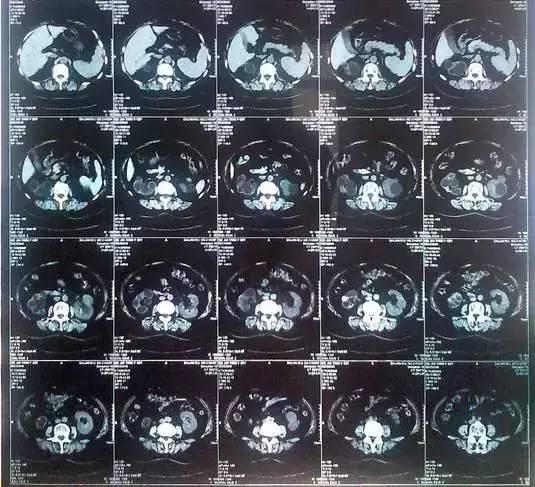

55歲的老何是金華東陽(yáng)市橫店鎮(zhèn)人,一名普通工人。因?yàn)轭l繁腰疼去醫(yī)院檢查,結(jié)果CT顯示,他的左腎里竟然密密麻麻布滿了石頭,幾乎把整個(gè)腎都塞滿了,手術(shù)從左腎取出了420顆結(jié)石!

醫(yī)生看了CT的結(jié)果顯示,非常嚴(yán)肅的告訴他,他的左腎已經(jīng)被結(jié)石占滿,必須馬上手術(shù)治療。這次手術(shù)讓主刀醫(yī)生觸目驚心,他們居然從老何的左腎取出了420顆結(jié)石。這是他們手術(shù)生涯上從來(lái)沒(méi)有遇到過(guò)的病例。